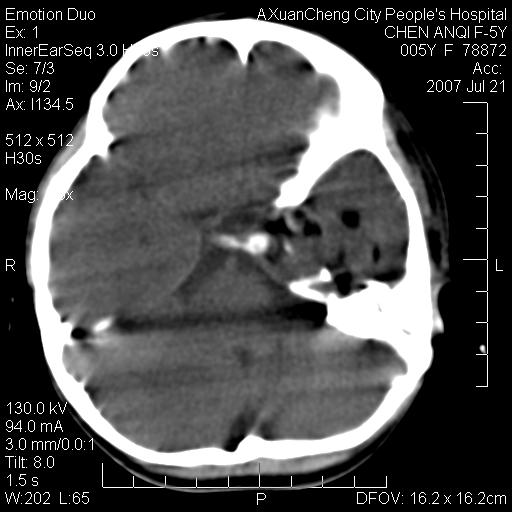

标题: PED0273:5岁,左耳流脓痛疼一周,颅底骨质破坏 [打印本页]

标题: PED0273:5岁,左耳流脓痛疼一周,颅底骨质破坏

患儿5岁,左耳流脓痛疼一周,左外耳道肉芽组织填塞 软组织窗显示病灶内结节状低密度影为气体密度

考虑中耳乳突炎并胆脂瘤形成可能。

左侧中耳炎并胆脂瘤,左颞骨岩部骨质破坏并颅内感染积气。